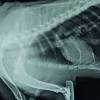

6 Most Common Cat Health Problems from img.webmd.com Straining to urinate or defecate. My neutered, dsh, soon to be 12 yr old cat has either fibrosarcoma or osteosarcoma in the hind leg. Unfortunately we don't have a lot of easy ways to assess for cancer in a cat's chest. The cat will have a dry cough and will be less active. They'll be able to find out if your cat really does and, if so, what type it is. They are not as useful for looking at the brain or spinal cord. If the cancer originates in other parts of the body, the coughing will not be present in the initial stages of the disease. Pulmonary carcinomas have a high tendency to metastasize, so full.

12 Warning Signs Of Cat Cancer Every Owner Should Know Pethelpful from images.saymedia-content.com My cat had a lung xray which showed a lot of calcification my cat had a lung xray which showed a lot of calcification in her lungs. Read on for some must know tips on how to do the best for your pet (and yourself) in this most difficult time. Cat lung cancer can be one of two types, either primary or secondary. You can recognize fluid in cat's lungs by evaluating your cats breathing. For example, certain breathing problems and coughing are surprisingly uncommon; Adenocarcinoma grows rapidly and metastasizes to distant parts of the body and organs, including the brain, eyes, bones, and lymph nodes. Because many cats and dogs may not show obvious signs of cancer pain and also tend to hide pain as a protective mechanism, identifying the degree of pain and the amount of suffering can be very difficult. Doc said it's definitely lung cancer, without using those words.

1 from Vets don't know what causes cat lung cancer, but they think pollution might be a causal factor. For tumors in the belly area, an ultrasound allows your vet to examine the whole area. But, there are other possibilities. Certain breeds are more predisposed to develop pulmonary tumors than others. The important thing to remember at this point is that your veterinarian thinks your cat has cancer but doesn't know it for sure. A benign tumor won't spread, while bone cancer metastasizes quickly. If your doctor thinks the cancer might have spread but doesn't know where. Xrays showed osteolytic lesions in the bone and a large soft tissue mass surrounding it.